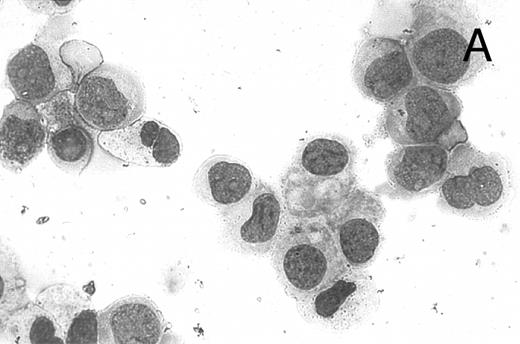

CD437 inhibition of HL-60R growth and induction of apoptosis.Although HL-60R cells are resistant to RA-mediated inhibition of growth,16,17 they are exquisitely sensitive to CD437-mediated inhibition of growth (Fig 1A) with as little as 25 nmol/L CD437 inhibiting growth by approximately 50% (Fig 1B). Similar inhibition of growth was noted in the parental HL-60 cell line (Fig 1C), as well as the RA-resistant K562 leukemia cell line28 (Fig 1D). As evidenced in Fig 1A, there was not only a total inhibition of cellular proliferation in the presence of CD437 but an actual cell loss. We therefore examined whether CD437 induced programmed cell death (apoptosis) in the HL-60R cells. That CD437 indeed induced apoptosis in the HL-60R cells was documented using three independent parameters. (A) HL-60R cells after exposure to 1 μmol/L CD437 displayed marked nuclear fragmentation and chromatin condensation, with the nuclear and cytoplasmic membranes remaining intact (Fig 2), a morphology indicative of apoptosis.29 (B) Incubation of HL-60R cells with 1 μmol/L CD437 resulted in internucleosomal cleavage and laddering of the DNA on gel electrophoresis (Fig 3), a hallmark of apoptosis.29 (C) A number of studies have suggested a critical role for cysteine proteases in the apoptotic process.30-37 Numerous substrates for this family of proteases have now been identified.37-41 PARP, which plays an important role in both DNA synthesis and repair, is cleaved early in the apoptotic process.37 38

CD437-induced apoptosis in HL-60R cells. HL-60R cells were grown as described in the Materials and Methods and exposed to either vehicle alone or CD437 (1 μmol/L) for 24 hours and then stained with aciridine orange. (A) Cells exposed to only vehicle. (B) Cells exposed to CD437 (1 μmol/L).

A number of antagonists and promoters of apoptosis have recently been described. The bcl-2 family, which now consists of 7 different proteins encoded by 7 different genes, has now been characterized (Vaux and Strasser37 and the references contained within). Bcl-2 and bcl-XL are expressed in numerous cell types and are potent antagonists of apoptosis. We were unable to detect bcl-XL expression in HL-60R or HL-60 cells as has previously been described,43 but found that bcl-2 is highly expressed in these cells and is also cleaved during CD437-mediated apoptosis (Fig 6). Phosphorylation of bcl-2 has been previously described as a mechanism for bcl-2 inactivation during the apoptotic process.44 Whether cleavage of bcl-2 represents another mechanism by which bcl-2 is inactivated remains to be determined. That this cleavage of PARP, CPP32, and bcl-2 does not simply represent random cleavage of a number of proteins is suggested by our inability to detect cleavage of lamin B (data not shown), which is often found cleaved in a variety of forms of programmed cell death.39 41 CD437 also markedly inhibited growth of the K562 cells (Fig 1C) but contrary to HL-60R cells apoptosis was not noted until 144 hours of exposure to CD437, as indicated by internucleosomal degradation demonstrated by gel electrophoresis (Fig 7). We also examined the ability of CD437 to induce PARP cleavage and apoptosis in primary leukemic blasts obtained from a patient with acute myelogenous leukemia. As shown in Fig 8C, enhanced PARP cleavage was noted within 24 hours after exposure to 1 μmol/L CD437, with the apoptotic morphology noted at 48 hours of exposure (Fig 8A and B).

CD437-mediated apoptosis in primary leukemia cells. Leukemic blasts were isolated as described in the Materials and Methods. Cells were exposed to 1 μmol/L CD437 for various periods of time and PARP cleavage was assessed as previously described. (A) Leukemic cells exposed only to vehicle for 48 hours. (B) Leukemic cells exposed to 1 μmol/L CD437 for 48 hours. (C) CD437-mediated PARP cleavage. Lanes 1 and 3, cells exposed to vehicle only for 24 and 48 hours, respectively. Lanes 2 and 4, cells exposed to 1 μmol/L CD437 for 24 and 48 hours, respectively.